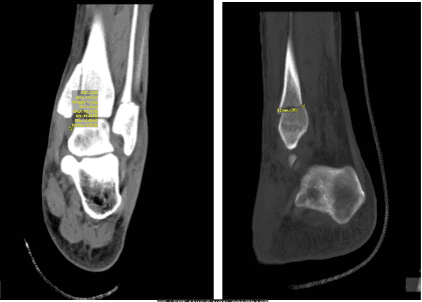

Patient presented his CT result and discussed it. Result showed Tri malleolar fracture on his left ankle. We discussed the treatment options for the patient’s diagnosis, which included: living with the extremity as it is, organized exercises, medicines, injections and surgical options.

CT-Left ankle non-contrast